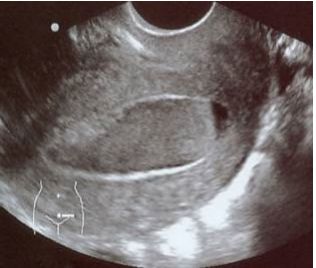

96 32 歲女性於 3 個月前因妊娠 2 個月合併胎死腹中而接受人工流產手術,術後至今尚無月經來過。近 2 日常感覺下腹陣發性疼痛,於今日加劇而就醫。經陰道指診發現子宮有觸壓疼痛的情形,尿液懷孕試 驗呈現陰性反應。經陰道超音波掃描子宮發現有附圖之情形,依據圖示此患者最適合之診斷為: (A)輸卵管水腫(hydrosalpinx) (B)輸尿管水腫(hydroureter) (C)子宮頸閉鎖(cervical canal stenosis) (D)子宮內膜增生(endometrial hyperplasia)